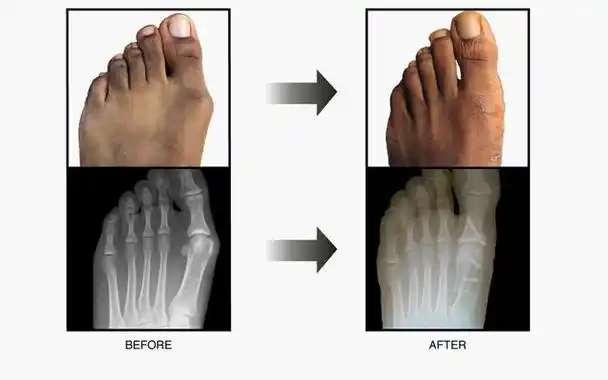

大脚拐,大脚趾内侧疼痛,要警惕:拇(趾)外翻,拇囊炎